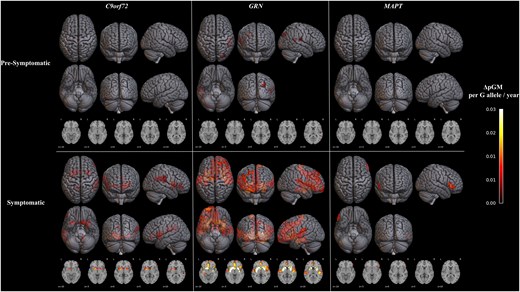

Mean age of participants was 47.9 ± 13.8 years, 58.1% were female and 61% had at least one G allele. C9orf72: rs1990622G allele dosage was associated with less atrophy within the right occipital region in presymptomatic carriers at baseline, and reduced atrophy rate within putamen and caudate nucleus, right frontotemporal regions, left cingulate and bilateral insular cortices in symptomatic carriers over time; lower NfL levels in presymptomatic carriers at baseline; better executive functions and language abilities in presymptomatic carriers; and maintained overall cognitive functions and behaviour in symptomatic carriers over time. GRN: rs1990622G allele dosage was associated with reduced grey matter atrophy rate within the right temporal and occipital regions in presymptomatic carriers, and within the right frontal cortex and insula over time in symptomatic carriers; lower serum NfL levels over time in presymptomatic carriers and lower NfL levels at both baseline and over time in symptomatic carriers; and better global cognitive performance at baseline and higher attention/processing speed scores over time in symptomatic carriers. MAPT: rs1990622G allele dosage was associated with reduced grey matter atrophy rate within the right inferior frontal gyrus in symptomatic carriers, but no effects on serum NfL or cognitive/behavioural measures.